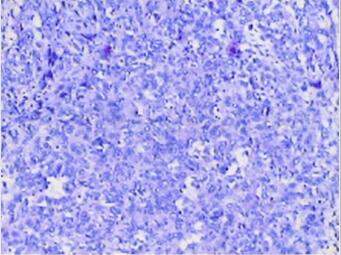

滑膜肉瘤(图4)

图4 病理:镜下:瘤细胞部分圆形,部分梭形,异型明显,间质有黏液,浸润性生长,有较多坏死。免疫组化:CK(+),Vimetin(+),Bcl-2(±),S-100(-),CD34(-),MyoD1(-),SMA(少许+)。诊断:(肘部)滑膜肉瘤

肉眼所见为圆形或分叶状,瘤结节位于肌肉内,部分可见假包膜;镜下主要由梭形细胞及上皮细胞构成,依据不同类型细胞所占比例不同分为梭形细胞为主型、上皮细胞为主型及混合型三种。